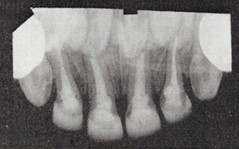

2. Determination of Working Length (WL)

“The distance from the coronal reference point to the point at which canal preparation and obturation should terminate.” – Glossary of Endodontic Terms.